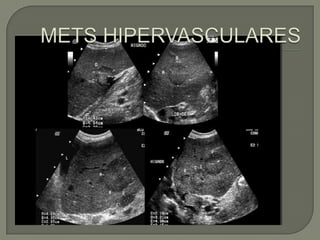

   Subgrupo de lesiones metástasis con importante

aportevascular.

   Similar aspecto a las hipovasculares, pero con

flujo importante a la valoración con Doppler color y

muchas veces son ecogénicas.

   Lostumores primarios con implantes hepáticos

hipervasculares mas frecuentes :

• Neuroendocrinos, sarcomas, células renales y melanoma.

• Neuroendocrinas: diferencial con hemangiomas

• Metástasis de melanomas: usualmente con sangrado

Subgrupo de lesiones metástasis con importante aportevascular.  Similar aspecto a las hipovasculares, pero con flujo importante a la valoración con Doppler color y muchas veces son ecogénicas.  Lostumores primarios con implantes hepáticos hipervasculares mas frecuentes : • Neuroendocrinos, sarcomas, células renales y melanoma. • Neuroendocrinas: diferencial con hemangiomas • Metástasis de melanomas: usualmente con sangrado